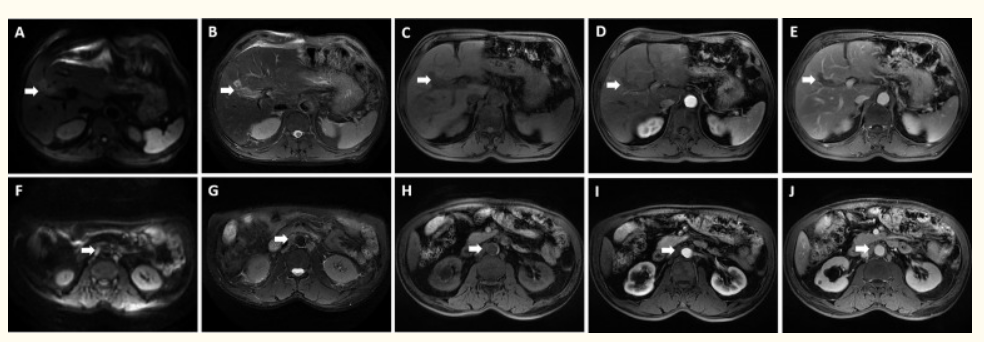

患者入院后进行进一步检查。脏器声学对比显示肝IV、V节实质低回声肿块,彩色多普勒血流显像(CDFI)显示血流信号。随后,增强CT和磁共振成像(MRI)显示肝脏V-VIII节段出现形态不规则的肿块(49 mm * 39.6 mm);肝门静脉和腹膜后淋巴结肿大,位于下腔静脉和腹主动脉之间的较大淋巴结(30.4 mm * 23.1 mm)。

经过多学科专家会诊(MDT),决定采用CisGem+仑伐替尼+替雷利珠单抗三联方案。因此,患者接受了4个周期的系统治疗,未出现明显并发症。此后不久,2020年9月3日,肝脏MRI显示,肝V-VIII节段病灶缩小,直径约15mm,边界清晰。此外,肝门静脉和腹膜后多发淋巴结转移,但与既往治疗相比明显减少。正如预期的那样,患者按照标准RECIST 1.1标准成功地获得了部分应答(PR)。